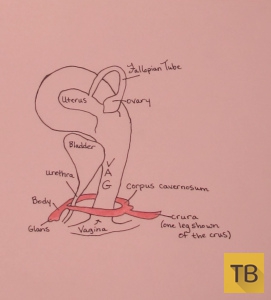

Научное название наружной «маленькой пимпочки» или «шишечки» головка. Этот маленький орган содержит около 8,000 чувствительных нервных волокон - больше чем где бы то ни было еще в человеческом теле и почти в два раза больше, чем в головке пениса! Из чтения работы Мари Бонапарт становится ясно, что она ошибочно полагала, что клитор полностью состоит из головки, а поскольку это единственная видимая часть клитора и к тому же сверхчувствительная, большинство современных женщин делают то же неверное заключение. Однако на самом деле большая часть клитора расположена внутри и состоит из двойного пещеристого тела (лат. corpus cavernosum clitoridis), двух ножек (лат. crus clitoridis) и двух клиторальных луковиц (лат. bulbus vestibuli vaginae).

Головка клитора переходит в тело внутреннего клитора, которое в свою очередь расходится в два пещеристые тела. В возбужденном состоянии пещеристые тела охватывают влагалище с обеих сторон, как если бы они крепко обнимали его!

Рисунок клитора в возбужденном состоянии (надписи на рисунке: Vagina или Va - влагалище, Uterus - матка Fallopian Tube – фаллопиева труба, Ovary - яичник, Bladder – мочевой пузырь, Urethra - уретра, Glans – головка клитора, Body – тело клитора, Corpus Cavernosum – двойное пещеристое тело клитора, Crura – ножка клитора).

Пещеристые тела уходят еще глубже, сходясь и вновь раздваиваясь, чтобы сформировать две ножки. В состоянии покоя эти ножки длиной до 9 см направлены в сторону бедер, при возбуждении они вытягиваются в сторону позвоночника.

Около каждой ножки с обеих сторон от входа во влагалище расположены клиторальные луковицы. Они находятся внутри тела под большими половыми губами. Когда они наполняются кровью, они замыкаются вокруг отверстия влагалища, вызывая набухание вульвы. Возбудите их и вы получите более возбужденный, более тесный вход во влагалище для исследования!

Рисунок клитора в возбужденном состоянии (надписи на рисунке: Vagina - влагалище Glans – головка клитора, Body – тело клитора, Corpus Cavernosum – двойное пещеристое тело клитора, Crura – ножка клитора).